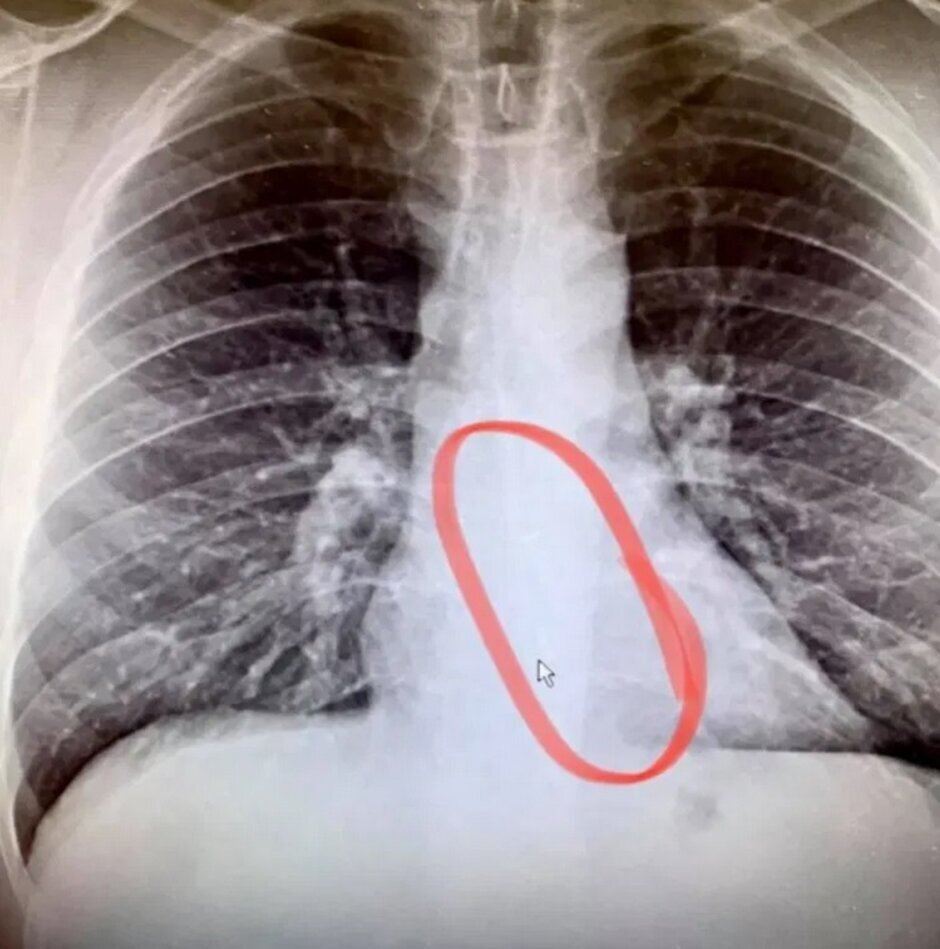

به پزشک مراجعه میکنند و گوتیه با انجام تصویر برداری رادیویی که پزشک انجام میدهد، گوتیه ایرپاد گمشدهاش را در مری خود پیدا میکند و با آندوسکوپی اضطراری که پزشکان انجام دادند ایرپاد را از مری او خارج کردند. نکته جالب اینجاست که ایرپاد همچنان کار میکند. کاربران باید به این نکته توجه داشته باشند که قبل از اینکه وارد رخت خواب خود شوند ایرپادهای خود را بردارند تا دچار آسیب دیدگی نشوند.